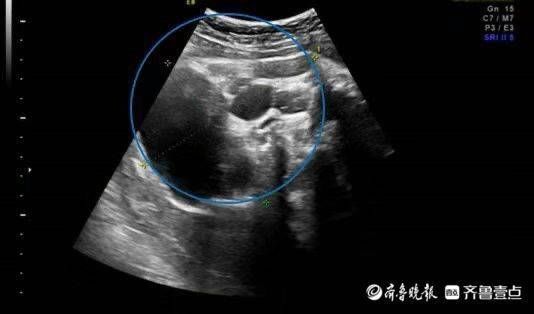

产检发现宝宝臀部有巨大肿瘤,直径达5厘米,近乎胎儿头颅大小,产妇不舍放弃孩子,被转诊到青岛妇儿医院胎儿医学门诊后,专家认为终止妊娠并不是唯一的选择,随后制定了相关手术管理方案。经过剖宫产,小宝宝顺利出生,并接受了手术,9月1日,宝宝康复出院。

几个月前,家住外地的准妈妈唐女士在当地医院产检时,超声发现肚里的宝宝患有骶尾部畸胎瘤,直径达5厘米,近乎胎儿头颅大小,当地医院建议终止妊娠。“二胎放开以来,我和我老公就一直想再要个孩子,好不容易怀上了,我们真舍不得。”唐女士说。抱着试试看的想法,唐女士被转诊到青岛妇儿医院胎儿医学门诊。

胎儿医学门诊立刻组织多学科会诊,小儿外科专家为唐女士一家介绍了畸胎瘤出生后的治疗,胎儿医学专家提供了宫内随访及监护方案。同时,产科专家为其制定了合理的分娩管理方案。在听到专家们专业全面的方案后,唐女士决定积极配合治疗。后期体检中,宝宝的畸胎瘤逐渐增长,分娩前最后一次超声提示畸胎瘤直径达10cm,但并未出现羊水过多等异常情况。